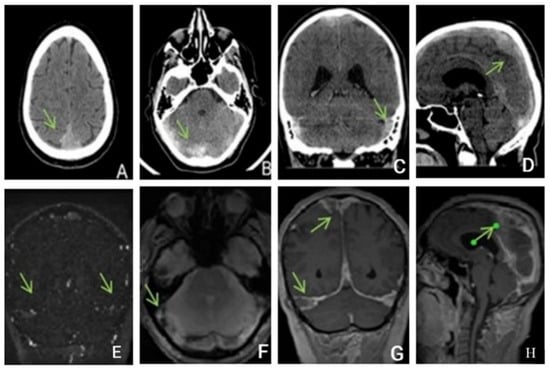

Native head CT performed at admission (Figure 4) showed increased dimensions of sinuses, and hyperdense content in the superior longitudinal sagittal sinus, the right sinus, and, contiguously, the inferior longitudinal sinus as well as in the right transverse sinus and partially the right sigmoid sinus. Additionally, a hyperdense appearance of the cerebellar tentorium raised the suspicion of a subarachnoid hemorrhage. The hypoattenuating brain tissue is suggestive of diffuse cerebral edema.

Figure 4. Unenhanced CT: (A,B)—axial, (C)—coronal, (D)—sagittal exhibits hyperdensity of the venous sinuses (sagittal superior and inferior, right sinus, transverse and sigmoid sinuses). (EH) MRI, (E)—TOF (time of fligt angiography) venous coronal; (F)—T2*hemo axial, (G)—T1 coronal after i.v. contrast, (H)—T1 sagittal after i.v. contrast, expressed extensive thrombosis of all veins.